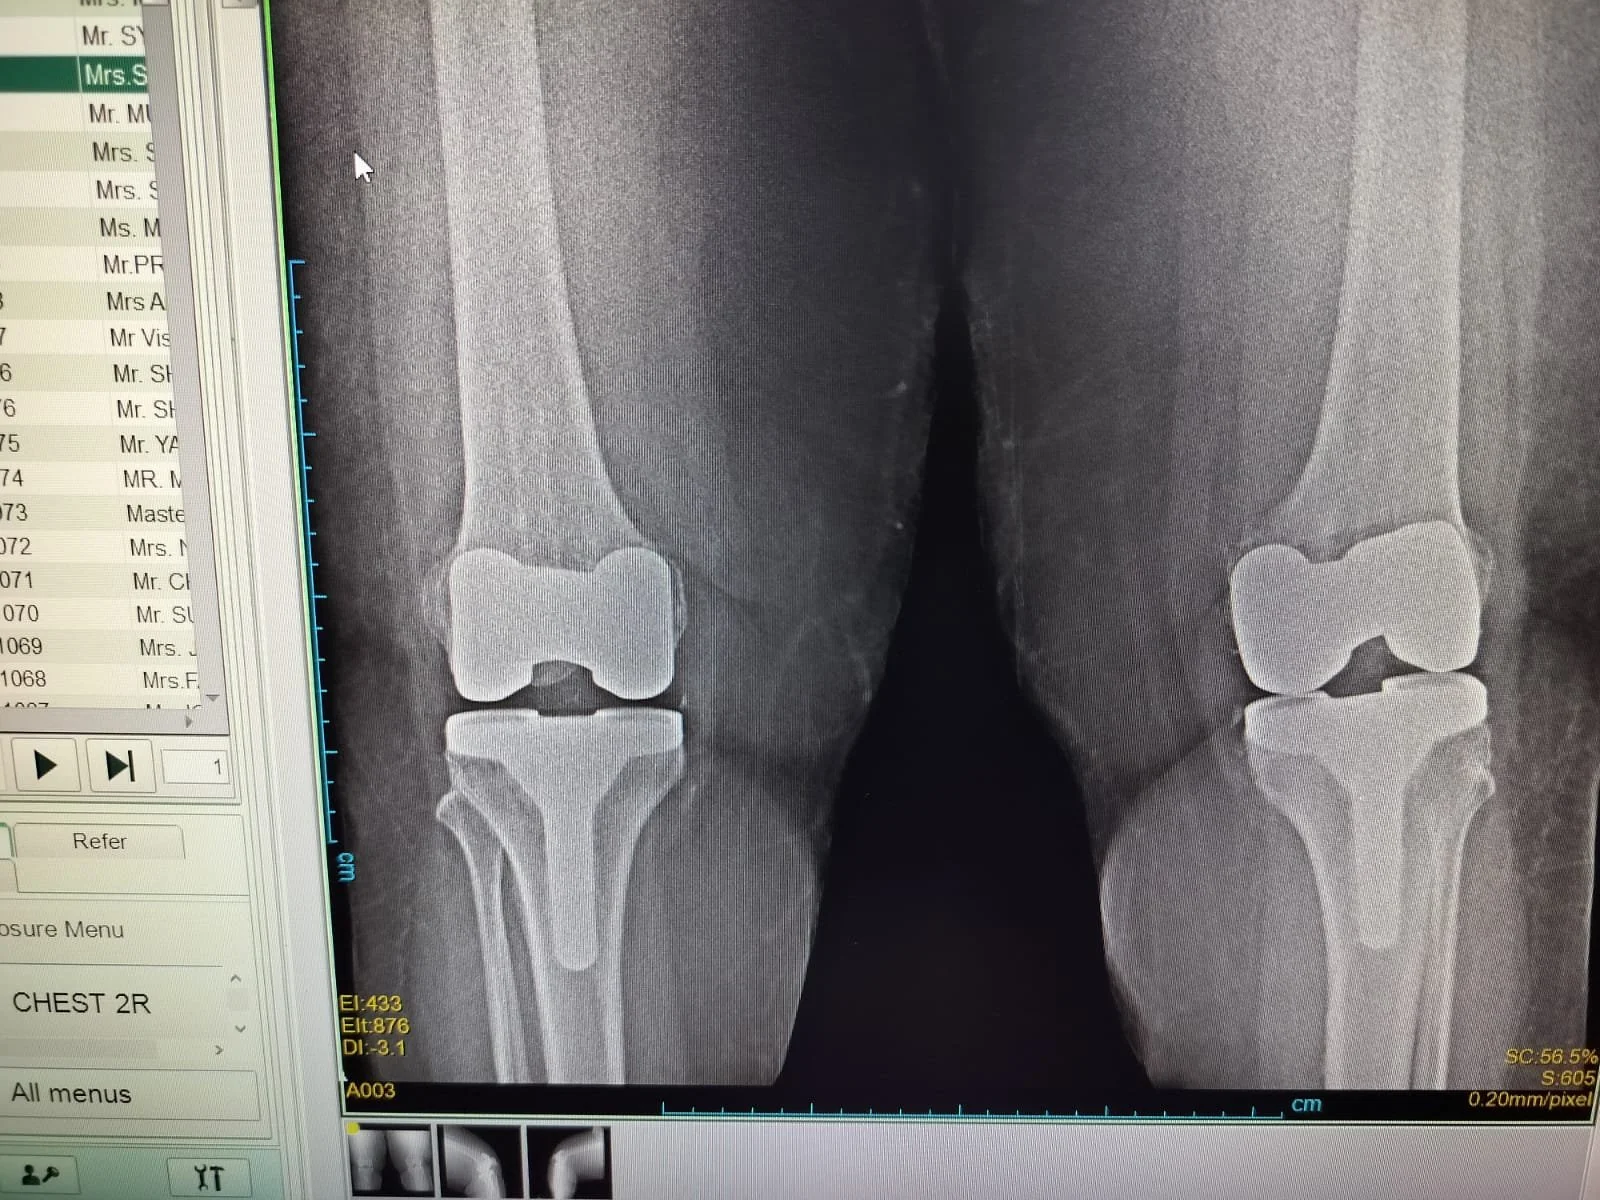

Bilateral Knee Replacement

Both knees replaced in a single surgery. Recommended for patients with severe arthritis in both knees, reducing overall recovery time and hospital stays.